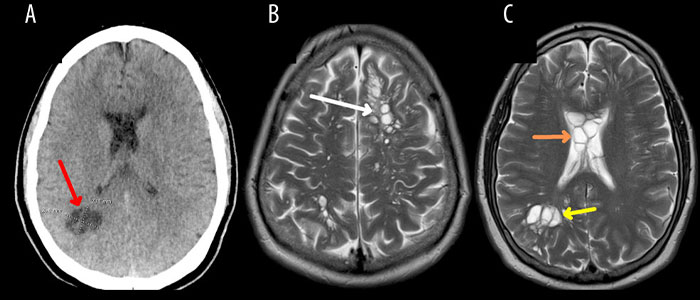

“It is very rare for patients to contract neurocysticercosis outside of classic exposures or travel, and such cases in the United States were thought to be nonexistent,” the report reads

Image credits: Tima Miroshnichenko

Neurocysticercosis is a leading cause of epilepsy in the developing world

Image credits: amjcaserep.com